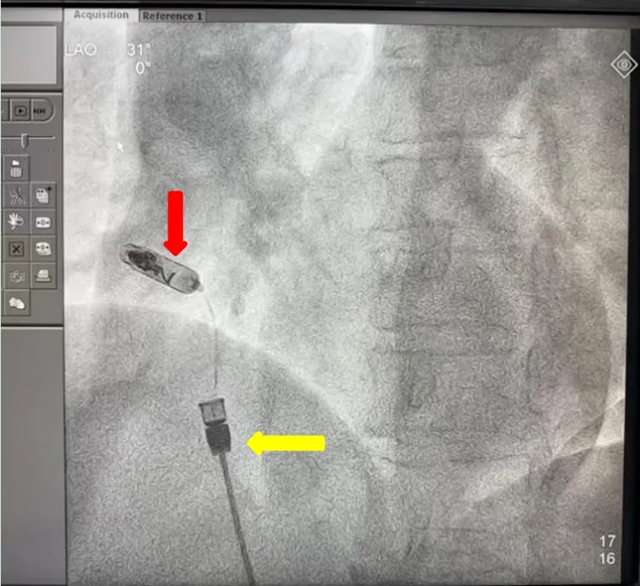

螺旋锚定:通过DSA影像引导,将起搏器的双螺旋电极精准旋入右心耳基底部,多角度X线透视确认位置稳固;

植入中

注:红色箭头为无导线起搏器,黄色为递送系统

术中影像